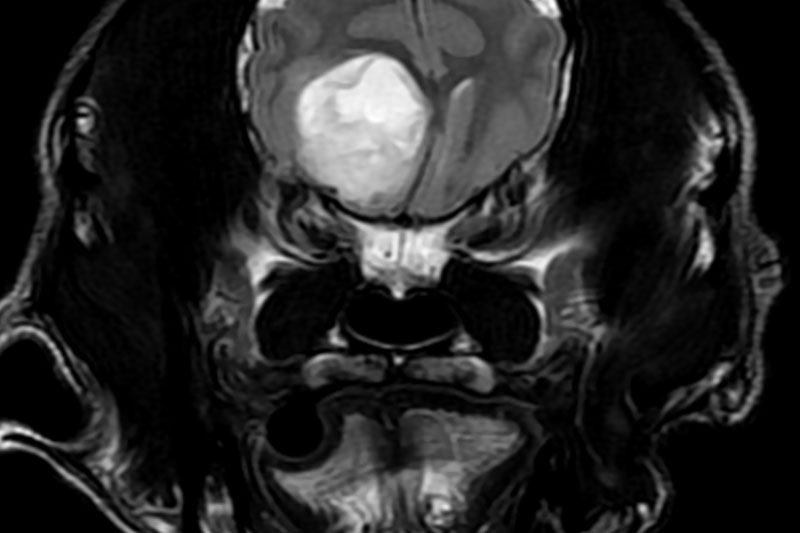

| 종양 조직 | 종양의 성질, 침윤 범위, 주위 조직과의 관계 확인 등 |

종양의 경계·성질·침윤 범위 세밀 평가